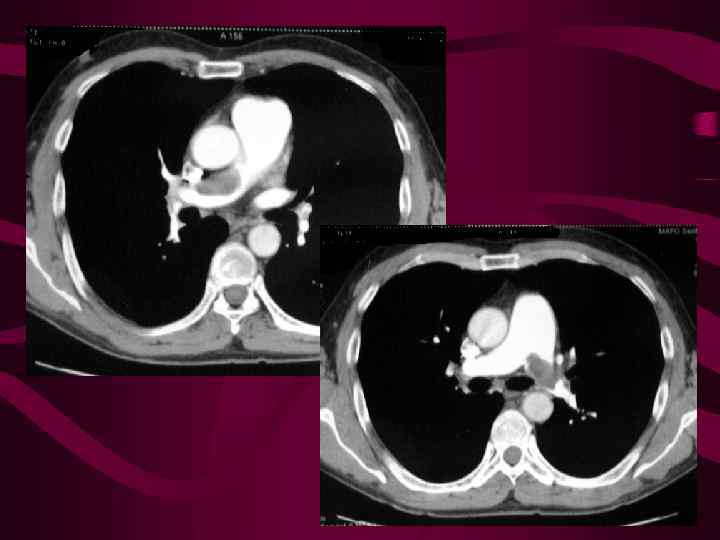

Саркома ЛА. КТ ангиография Инфаркт S 6 справа. В просвете ЛА справа дефект наполнения с Частичным сохранением кровотока

Саркома ЛА. КТ ангиография Инфаркт S 6 справа. В просвете ЛА справа дефект наполнения с Частичным сохранением кровотока